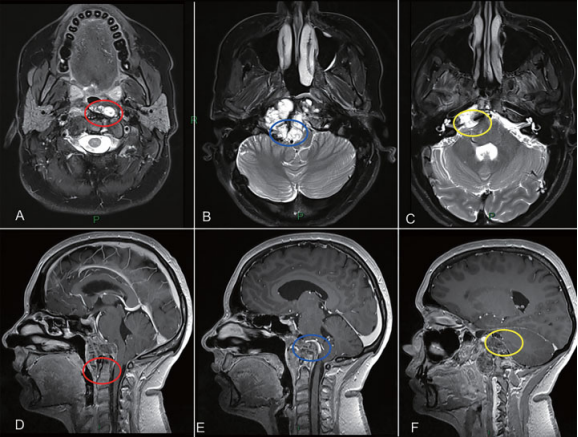

图2:颅颈交界区肿瘤手术策略分析。肿瘤旁正中部分可经鼻内镜切除。齿状突周边肿瘤(A和D红圈)、侵犯硬膜内部分与后循环接触的肿瘤(B和E蓝圈)及既往乙状窦后入路手术粘连区肿瘤(C和F黄圈),更适合二期远外侧开颅切除。